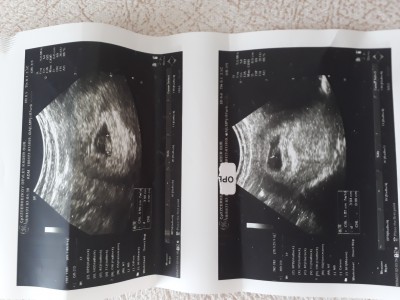

Merhaba dun doktora gttim arkadaslar ikiz  bebek sahibi olcagimi ogrendim saskinliktan çift mi tek mi sormadim  sizce cift yumurta ikizimi yoksa tek mi

Gebelik haftası 7+2

Tek gibi geldi canım

Tek görünüyor hayırlısı olsun inşallah

Tek yumurta canım çift olsa 2 kese görünürdü tek kese var Allah sağlıkla zamanında kucağına almayı nasip etsin

Merhaba bende ikiz gebelik var dedi doktor iki kese var bende sizinki tek duruyor sizin adet tarihinizle gebelik keseniz uyuşuyor mu bende geriden geliyor Merak ediyorum

Kese tek canım tek yumurta ikizi❤